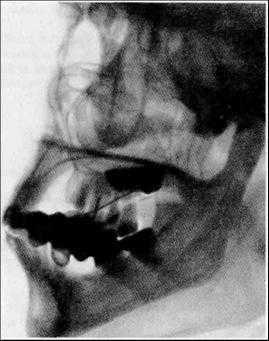

Рентгенографию тела и ветви нижней челюсти в боковой проекции проводят на дентальном рентгенодиагностическом аппарате.